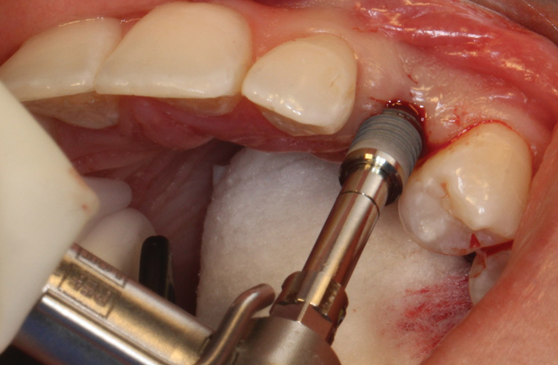

(35.) An implant being inserted into the prepared osteotomy of a patient who presented for the replacement of the maxillary left central incisor.

Figure 35